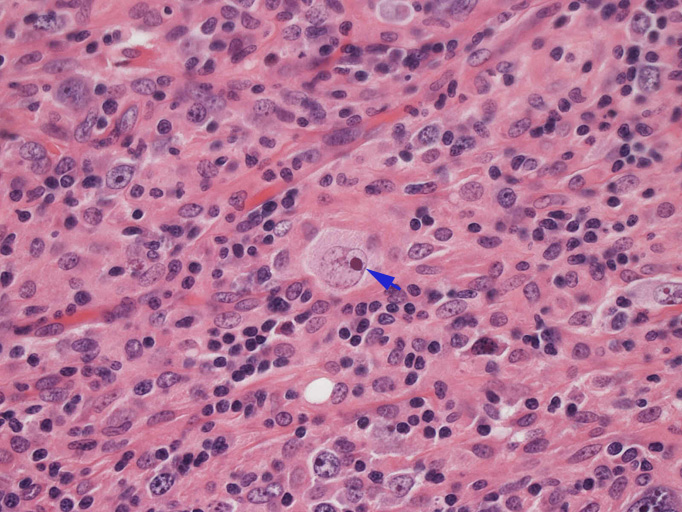

結節構造内では, 好酸性細胞質をもつ組織球の増生を背景に大型異型細胞が散在性または集蔟して増殖している。被膜下にも線維化組織内にbizzarreな大型細胞が認められる。リンパ球は小型リンパ球が大型異型細胞を含む組織球性の結節辺縁に存在する。大型細胞は, centroblastic cellが多く, その他 Hodgkin cell-like cell, RS細胞様巨細胞, 腎臓型の核をもった細胞, 多型核の細胞など多彩な形態を示す。異型核分裂像をふくむ核分裂像が多い。

大型異型細胞の形態

| Hodgkin cell-like | centroblastic | centroblastic | multinucleic |

| anaplastic large | kidney-shaped | mirror image | atypical mitosis |